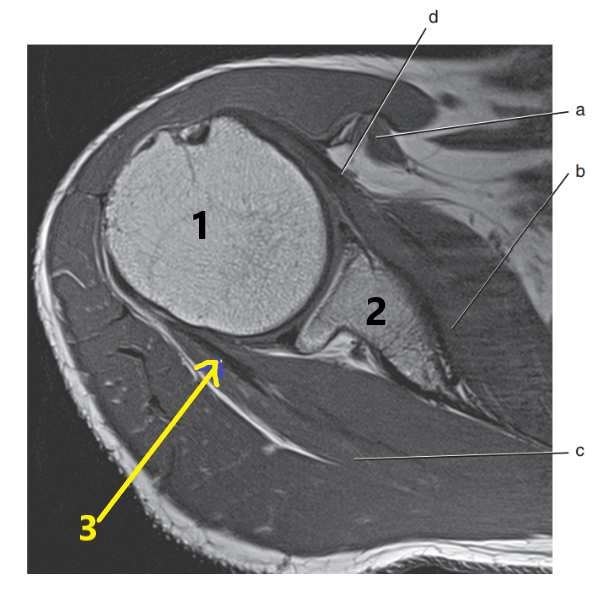

What is # 3 ?

Radius

What is # 1 ?

humerus

What is # 2 ?

Acromion Process

What is letter A?

Brachial artery

What is letter B pointing to ?